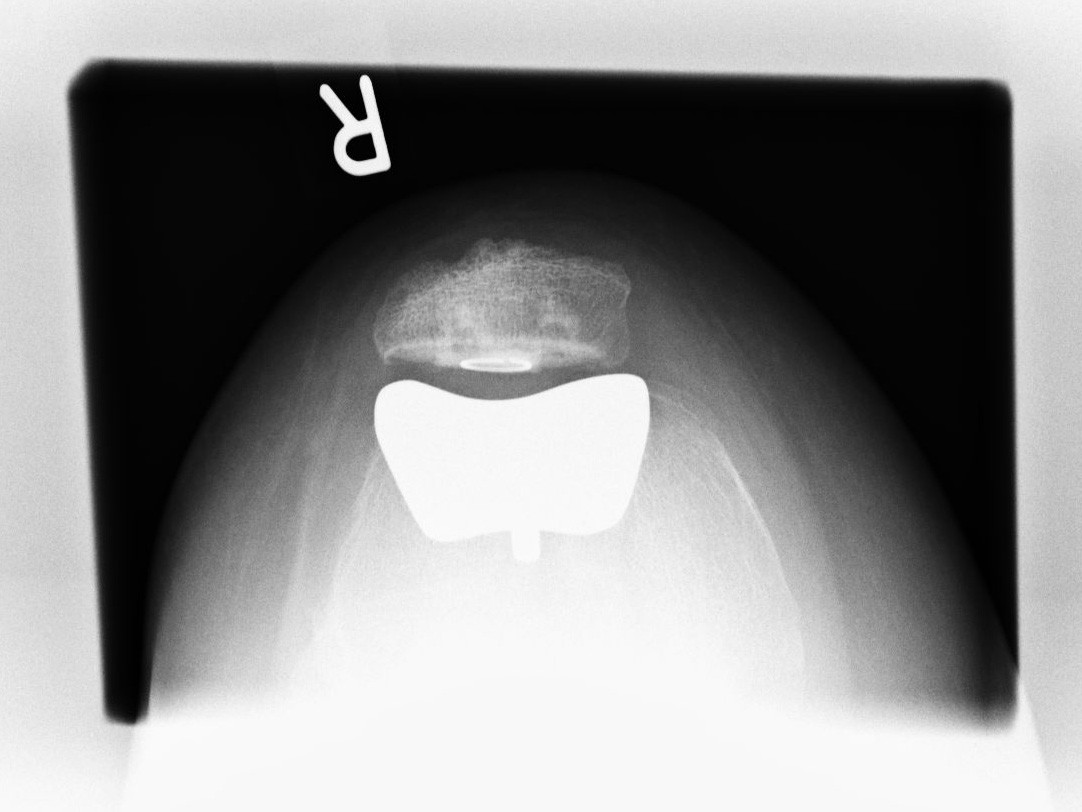

Teilgelenkersatz des Kniescheibengleitlagers („Femoropatellarersatz“)

Bei vielen Patienten ist nur der Anteil hinter der Kniescheibe von einem fortgeschrittenen Verschleiß betroffen. Hier gibt es die Möglichkeit einen Ersatz dieser Gelenkflächen hinter der Kniescheibe und korrespondierend dazu das Gleitlager für die Kniescheibe am Oberschenkel zu ersetzen. Hierbei bleiben sämtliche Bänder, Menisken sowie der innere und äußere Gelenkanteil intakt.

Ersatz der Kniescheibenrückfläche

In manchen Fällen entwickelt sich nach Ersatz des Kniegelenkes ein Schmerzsyndrom hinter der Kniescheibe z.B. durch einen fortschreitenden Verschleiß in diesem Bereich. Hier wird dann der isolierte Ersatz der Kniescheibenrückfläche empfohlen.